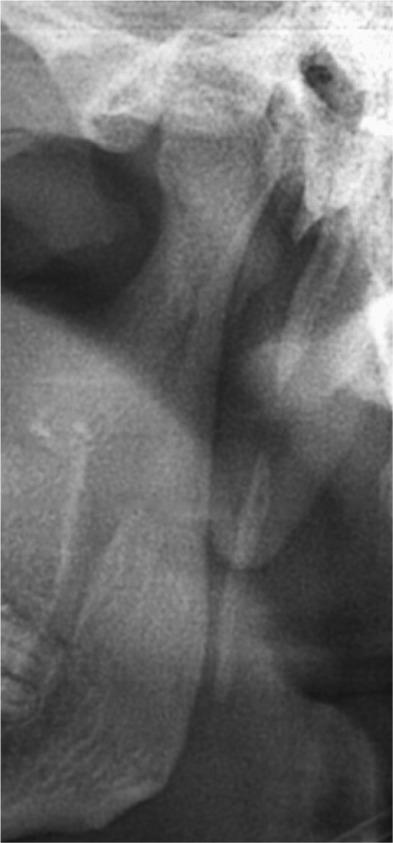

The objectives of this study were to assess the elongation of the styloid process on digital panoramic radiographs and to evaluate the prevalence of the elongation according to age, sex and types.

Digital panoramic radiographs of 198 geriatric edentulous patients were analyzed. The radiographic length of the styloid process was measured on both sides using the measurement toolbars on the accompanying analysis software. For statistical analysis, Student's -test, chi-square test and analysis of variance test were used.

The elongated styloid process was seen in 87 of the 198 patients. It was observed that as age increased, elongation of the styloid process increased with a male predominance. Type I elongation was more common than other types of elongation. Bilateral elongation was most commonly found than unilateral elongation, and both types of elongation were frequently seen in males compared with females.